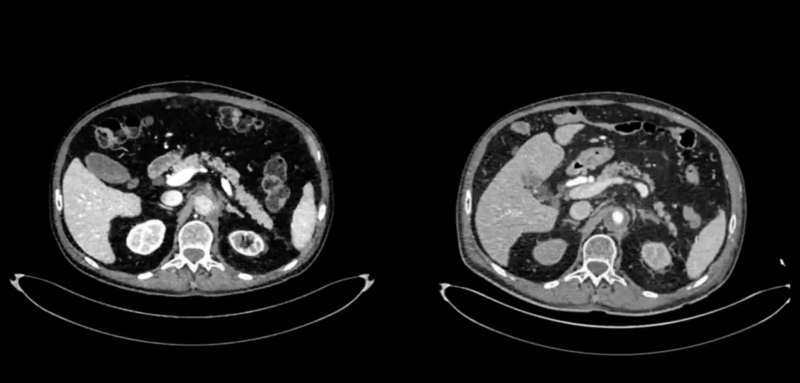

On the left: the acute complete aorto-visceral and aorto-iliac thrombosis.

On the right: restored flow in the superior mesenteric artery, both renal arteries, and the entire aorto-iliac axis after visceral aortic endarterectomy and aorto-bifemoral bypass.”